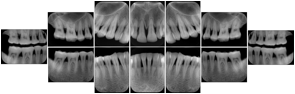

3. A dental provider wishes to capture a series of DICOM IO images for the patient’s dentition. The tooth morphology, teeth are divided into molars, premolars, canines and incisors, and a number of images for each jaw. The anatomic information was captured utilizing the triplet of schema. This standard code sequence is based on ISO 3950-2010, Dentistry - Designation system for teeth and areas of the oral cavity.

Every IO image should have anatomic information either through the primary or modifier sequence.

In most standard cases, images are oriented in structured layouts. These structured displays are useful to be shared between providers for reference purposes.

Table OO.1.1-1 shows structured display standard templates, where Viewset ID is based on the Japanese Society for Oral and Maxillofacial Radiology (JSOMR) classification provided by JIRA (Japan Medical Imaging and Radiological Systems Industries Association, www.jira-net.or.jp). Expected or typical teeth to be imaged location, region and designation codes are based on ISO 3950-2010, Dentistry - Designation system for teeth and areas of the oral cavity. For all the hanging protocols listed in OO.1.1-1, the value to use for Hanging Protocol Creator (0072,0008) is "JSOMR" and the value to use for Hanging Protocol Name (0072,0002) does not include "JSOMR" (e.g., "DL-S001A", not "JSOMR DL-S001A").